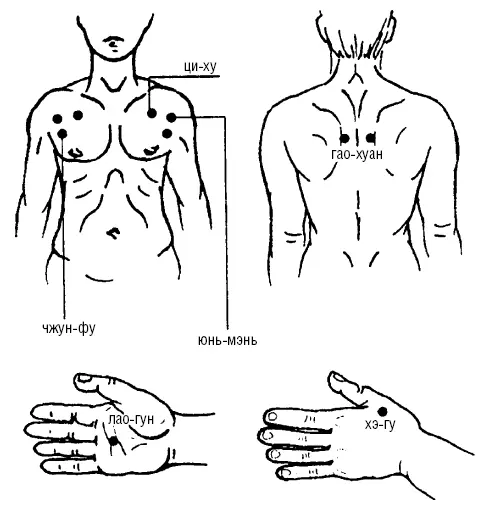

Рис. 112. При купировании приступа удушья (приступ бронхиальной астмы, нарушение дыхания)

Методика точечного массажа направлена на расслабление, тормозным способом отдельных групп мышц, участвующих в акте дыхания, призвана улучшить кровообращение, вентиляцию легких, что значительно способствует облегчению состояния массируемого (рис. 112):

1. ЦИ-ХУ (Е-13) находится на середине нижнего края ключицы, на 3 цуня от средней линии груди, по уровню второй сосковой линии.

2. ЮНЬ-МЭНЬ (Р-2) находится в подключичной ямке у нагрудного края ключицы.

3. ЧЖУН-ФУ (Р-1) находится на 1,5 цуня ниже, от наружного края ключицы в дельтовидно-грудной борозде, снаружи от второго ребра груди.

4. ХЭ-ГУ (GI-4) находится на вершине возвышения, образованного при сжатии первого и второго пальцев кисти, на тыльной ее стороне.

5. ЛАО-ГУН (МС-6) находится в центре ладонной поверхности кисти, при сжатии пальцев в кулак между третьей и четвертой концевыми фалангами, на линии «головы».

6. ГАО-ХУАН (V-43) находится в области спины, между Д 4_5/ 2по 2-й линии, на 3 цуня наружу от средней линии спины.